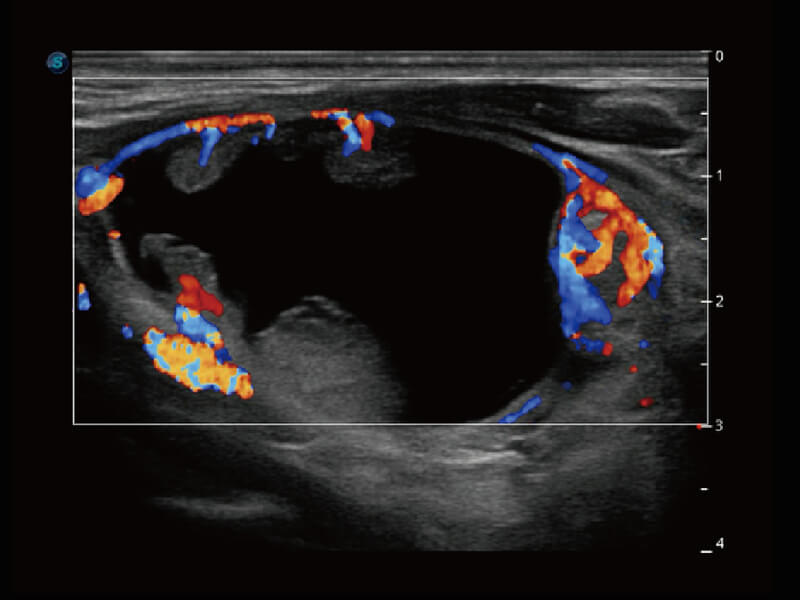

Micro F 显微血流成像 明察秋毫